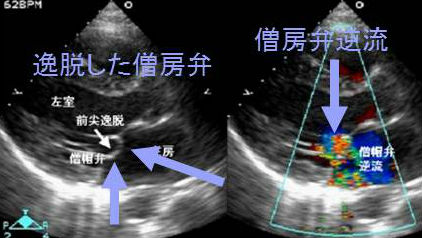

僧帽弁逸脱症は人口の5-10%に存在し、女性は男性の2倍です。よって循環血液量・心拍出量が増加する甲状腺機能亢進症/バセドウ病、非自己免疫性家族性甲状腺機能亢進症に合併する率も高くなります。(J Clin Endocrinol Metab. 1999 Apr;84(4):1459-62.)

未治療甲状腺機能亢進症/バセドウ病の30~40%との報告があります。

ほとんど無症状ですが、胸痛・不整脈による動悸もおこし、甲状腺機能亢進症状と紛らわしいです。

僧帽弁閉鎖不全・感染性心内膜炎(原因の1/3)をおこすと予後不良(突然死、敗血症など)。

聴診で収縮中期クリック・収縮後期雑音があれば疑わしく、心エコーすべきです。胸痛や不整脈による動悸に甲状腺機能亢進症と同じくベータ遮断薬が有効です。